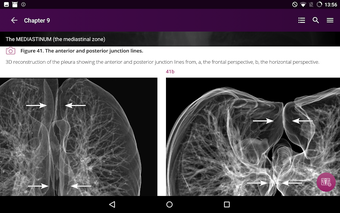

Radioloji'yi Keşfet: Göğüs Röntgeni Yorumlama, göğüs röntgeninin yorumlanmasının anlaşılmasını artırmak için tasarlanmış bir eğitim uygulamasıdır ve doktorlar, tıp öğrencileri ve radyologlar tarafından kullanılması amaçlanmaktadır. Uygulama, en küçük detayları görüntülemek için yakınlaştırılabilecek yüksek kaliteli görüntüler ve her bulgunun önemini anlamanıza yardımcı olacak bir sesli yorum içerir.

Uygulamanın amacı, kullanıcıların farklı x-ışını bulgularını ve bunların bir hastalığın teşhisinde nasıl kullanılabileceğini daha iyi anlamalarına yardımcı olmaktır. Uygulama, göğüs röntgeni yorumlaması için gerekli çeşitli yapı taşlarını kapsayan 5 bölüme ayrılmıştır.